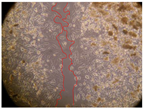

In the present study, the healing potential of 8 decoctions used in the preparation of ayahuasca was evaluated, using the wound scratch test. The evolution of the scratch created was monitored using microscopic images (Table 2) and the distance between the margins of the lesion was calculated (Table 3). Analysing the images that showed the evolution of the distance between the margins of the lesion and comparing them with the control samples, it was possible to verify that, in general, all the samples showed a great decrease in the lesion, and after 24 h of incubation, the samples of M. hostilis + P. harmala at 500 mg/L and P. viridis + B. caapi at 250 mg/L showed the best results. However, analysing the evolution of the distance calculated, only the sample of the commercial mixture at 250 mg/L after 2 h of incubation did not show a significant decrease. All other samples at different evaluation times, as well as the commercial mixture at 250 mg/L at the other times (8 h, 12 h and 24 h) showed a significant decrease in lesion margins compared to the control.

Table 2.

Microscopic images obtained from the scratch wound-healing assay with the samples of ayahuasca (magnification: 100×). The margins of the scratch appear in red.

These results are indicative of the healing activity of the samples tested. It is possible to observe in the images of Table 2 the migration of the fibroblasts incubated with the samples at different concentrations. In these images, it was possible to verify that the lesions closed over time, which was in accordance with the distance calculated between the margins of the lesion. As far as we know, to date there are no studies where the healing potential of ayahuasca has been evaluated, and it is not possible to compare the results now obtained. However, these results can be explained by the antioxidant and anti-inflammatory activity previously studied in these samples [], since it is reported that antioxidant activity and healing properties coexist in plant extracts []. Wound healing consists of the reconstruction of the lesion, involving several interactions between epithelial cells, growth factors, cytokines and chemokines. It has been reported that natural products, namely plant extracts, are involved in the proliferation of fibroblasts and keratinocytes, and may contain cell adhesion molecules, growth factors and cell signalling molecules, which can promote lesion reconstruction []. This in vitro assay, which, unlike conventional assays used to determine the healing properties of plant material, was non-invasive, allowed the screening of several samples with antibacterial, anti-inflammatory and antioxidant properties, which are important in wound healing [,].